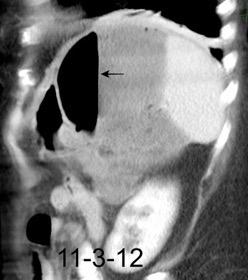

Diafragma “colgante” (“dangling sign”)

(“Dangling sign”)

TC. Mejor con multicorte. (reconstrucciones).

Asociación: Aire en pared.

Fracturas costal .Rotura esplénica. Neumoperitoneo.

Diafragma discontinúo Herniación de la grasa omental

Desser TS et al.The dangling diaphragm sign: sensitivity and comparison with existing CT signs of blunt traumatic diaphragmatic rupture. Emerg Radiol 2010